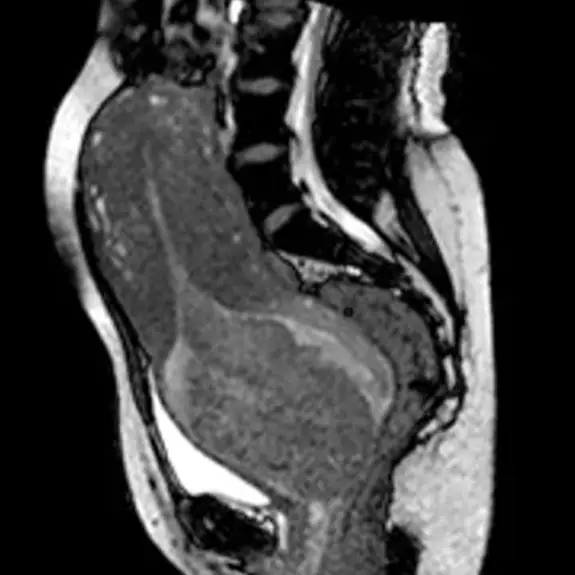

Published in a May 2012 copy of European Radiology, the story recaps how a German woman gave birth in an MRI back in 2010.

Remembering just how tight things are inside a traditional MRI, the team had to widen its mouth to help occupy the mother-to-be and the obstetrician. They also had to take the metal out of the fetal heart monitor so that it wasn't interrupted by the scanner's magnet, while sheeting was provided to protect the machine from 'fluid' leaking.

As reported by Scientific American, the 24-year-old woman wore earmuffs to shield her from the loud sound of the machine. As soon as the baby's head appeared, the machine was shut down to protect its own delicate ears.

Apparently, the hardest part of the whole thing (apart from the actual woman having to give birth) was getting her to keep still to ensure the images were as clear as possible.

The best images came from just before and after the birth, with one showing the baby's head going toward the birth canal.

Notably, this world-first captured the contortions of the uterine muscles and how the fetus rotated on its way toward the outside world.

Researchers noted the images showed "how extensively the rectum and adjacent muscles are pushed against the coccyx to enable the child to pass through the birth canal."